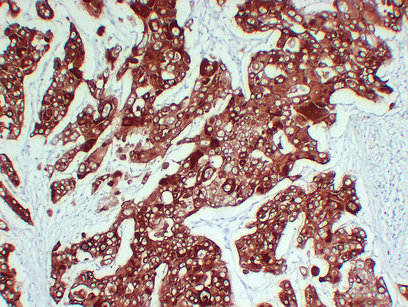

Immunohistochemistry analysis of paraffin-embedded Lung squamous cell carcinoma using Cytokeratin 6A antibody.High-pressure and temperature Sodium Citrate pH 6.0 was used for antigen retrieval.